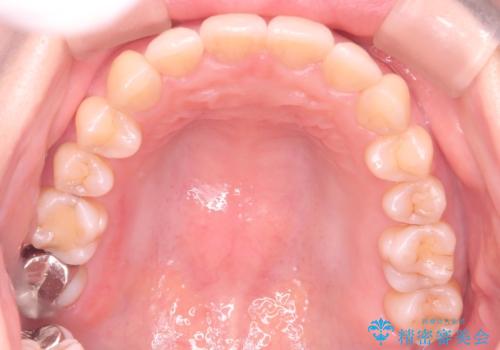

- 前歯の翼状捻転の改善を希望してこられた患者様です。

下顎の叢生はインビザラインで解決することがきましたが、上顎の捻転が完全には改善できなかったため、上顎は途中からワイヤーを用いて治療を行っています。

捻転の改善はインビザラインで苦手とするところですので、うまく治らない場合はワイヤーを提案しています。